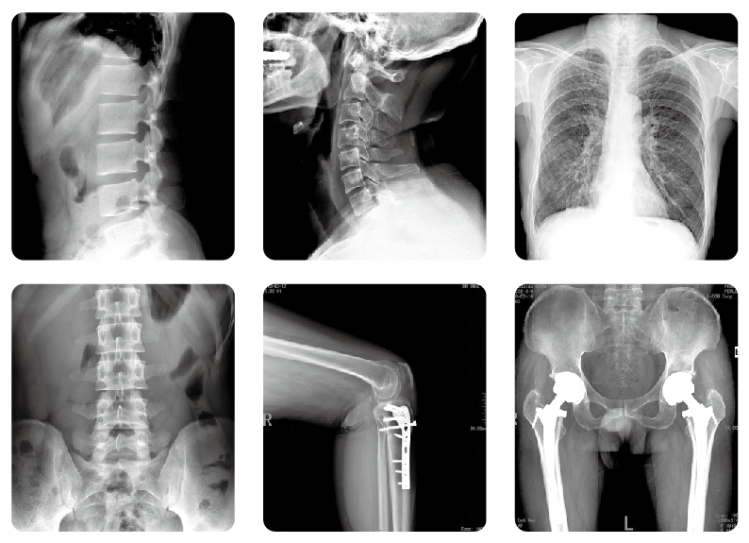

在門診,經(jīng)常會有拍片子的患者咨詢:大夫,放射科是不是到處都是射線,對我身體很不好啊?每次聽到諸如此類的問話,醫(yī)生都會有些哭笑不得,醫(yī)院放射科什么時候變得這么“恐怖”了?那么,放射科的走廊和候診區(qū)這些位置到底有沒有射線呢?會不會對人身體造成損害呢?

放射科拍片

其實,放射科的墻壁、門窗以及天花板都是特別訂制的。放射科的墻壁是加厚的,且涂抹上摻有硫酸鋇的材料,能屏蔽和消減輻射,門窗上也都鑲有鉛板,所以,除工作室內(nèi)有少量軟射線之外,過道以及走廊、等候區(qū)等位置是沒有射線的,因此,大可不必過度擔心。那我們平時拍一張普通X線檢查的輻射有多大呢?

拍攝一張普通X光胸片,其曝光率約為0.045mSv/S。拍攝一張胸部肋骨大約需要0.5S,因此接受一次胸部X線檢查,患者需要承受0.023mSv的輻射量。根據(jù)國際放射委員會制定的標準,輻射總危險度為0.0165/Sv,也就是說,身體每接受一西弗特(1Sv=1000mSv)的輻射劑量,就會增加0.0165的致癌率,以此推算,一張胸片會增加約為千萬分之零點六的危險。對其他醫(yī)學檢查來說,四肢約為0.01mSv,腹部為0.154mSv,骨盆為0.66mSv,腰椎為1.4mSv,上消化道為2.55mSv。因此單次醫(yī)學檢查導致健康人群患癌的風險在千萬分之一到十萬分之一之間。

放射科DR設備

況且,現(xiàn)在各大醫(yī)院均已全面采用DR設備,輻射劑量較普通X線照片大幅減少,常規(guī)放射檢查的劑量更在安全范圍內(nèi)。所以,除特殊個體(如懷孕早期)外,我們普通人一般不需要考慮輻射損傷的問題,完全可以安心就診。